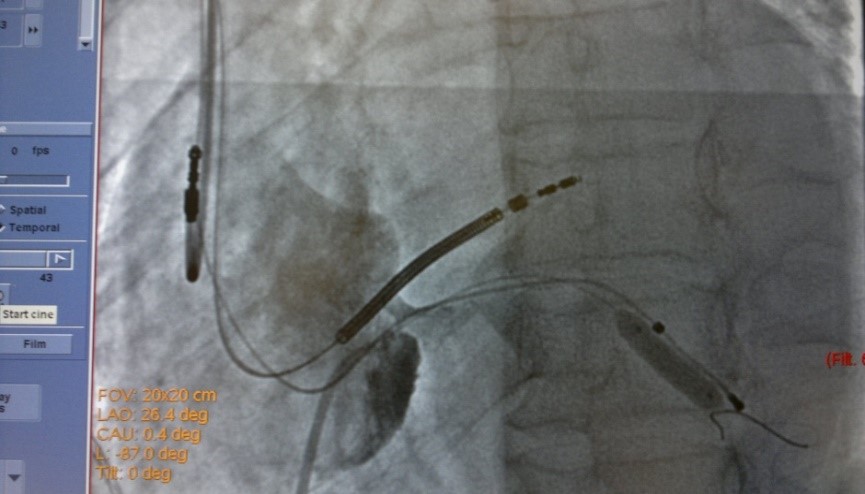

19.08.2015 выполнена попытка имплантации СРТ-D устройства, имплантировать ЛЖ электрод в заднею вену сердца не представилось возможным ввиду многократных смещений ЛЖ электрода в КС. Через 7 дней, вторым этапом, аритмологами и ренгенхирургами принято решение о имплантации ЛЖ электрода в заднюю вену ЛЖ с фиксирующим стентированием ЛЖ электрода в задней вене ЛЖ. Под м/а выполнен разрез в левой подключичной области по п/о рубцу. Выделен и выведен в рану ИКД. Пунктирована подключичная вена из раны. Желудочковый дефибриллирующий электрод активной фиксации позиционирован и вкручен в область МЖП 15 мV (с целью достаточного межэлектродного расстояния) [3], порог стимуляции желудочков 0,8 мА. В ПП по системе доставки доставлен катетер для КС, установлен в КС. Выполнена ангиография коронарного синуса (рис.1) – доступна единственная задняя вена ЛЖ, размером более 4 мм. ЛЖ электрод заведен через систему доставки и установлен в заднюю вену ЛЖ по коронарному проводнику. Порог стимуляции ЛЖ-2.0 мА, порог чувствительности 16.6 мВ. Стимуляции диафрагмального нерва нет. При попытке удаления системы доставки, последний дислоцируется в КС. Множественные попытки имплантации ЛЖ электрода безуспешны в связи с дислокацией последнего. При имплантации в дистальное русло порог ЭКС >6мА. ЛЖ электрод установлен в дистальное русло ЗВЛЖ по коронарному проводнику. Принято решение о фиксирующем стентирование ЛЖ электрода в ЗВЛЖ. Под м/а пунктирована v.f.s., установлен интродьюсер 6 Fr. К устью КС подведен проводниковый катетер JR4 6FR. В дистальное русло ЗВЛЖ проведен коронарный проводник (рис.2). По проводнику в ЗВЛЖ заведен стент 4.5-16 mm, выполнена имплантация (рис.3). При контрольной ангиографии диссекций не выявлено, стент расправлен полностью. Под контролем Rg-скопии и на раздутом баллоне удалена система доставки ЛЖ электрода, ЛЖ электрод стабилен (рис.4), порог ЭКС-0.8 мА (до стентирования 1,5 мА), сенсинг 10 мВ. Электроды фиксированы в ране. Подключен CRT-D и помещен в прежнее ложе над грудными мышцами. На ЭКГ эффективная бивентрикулярная стимуляция.

Рис.3. Рентгеновский стоп-кадр при имплантации стента в заднюю вену ЛЖ для фиксации левожелудочкового электрода. Наиболее оптимальное расположение ЛЖ электрода.